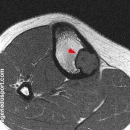

IRM :

En IRM, l'étude de Jee a porté sur 19 patients.

- signal en T1 et T2 dépend, de la présence d'hémosidérine, de la quantité de tissu cellulaire actif, de la quantité de collagéne, d'histiocytes spumeux et de la trabéculation osseuse.

- En T1, tous les FNO sont en hyposignal, parfois zones focales en hypersignal en rapport avec des phénomènes de saignement locaux

- En T2, 15/19 (79 %) sont en hyposignal ; et 4/19 en hypersignal. On peut retrouver sur cette séquence des dépôts d'hémosidérine et des septations internes trés caractéristiques

- après injection de Gadolinium, prise de contraste chez 15 patients (hétérogéne dans 12 cas et homogéne dans 3 cas)

- la présence d'un œdème du spongieux péri-lésionnel est possible et traduit alors le plus souvent une fracture pathologique